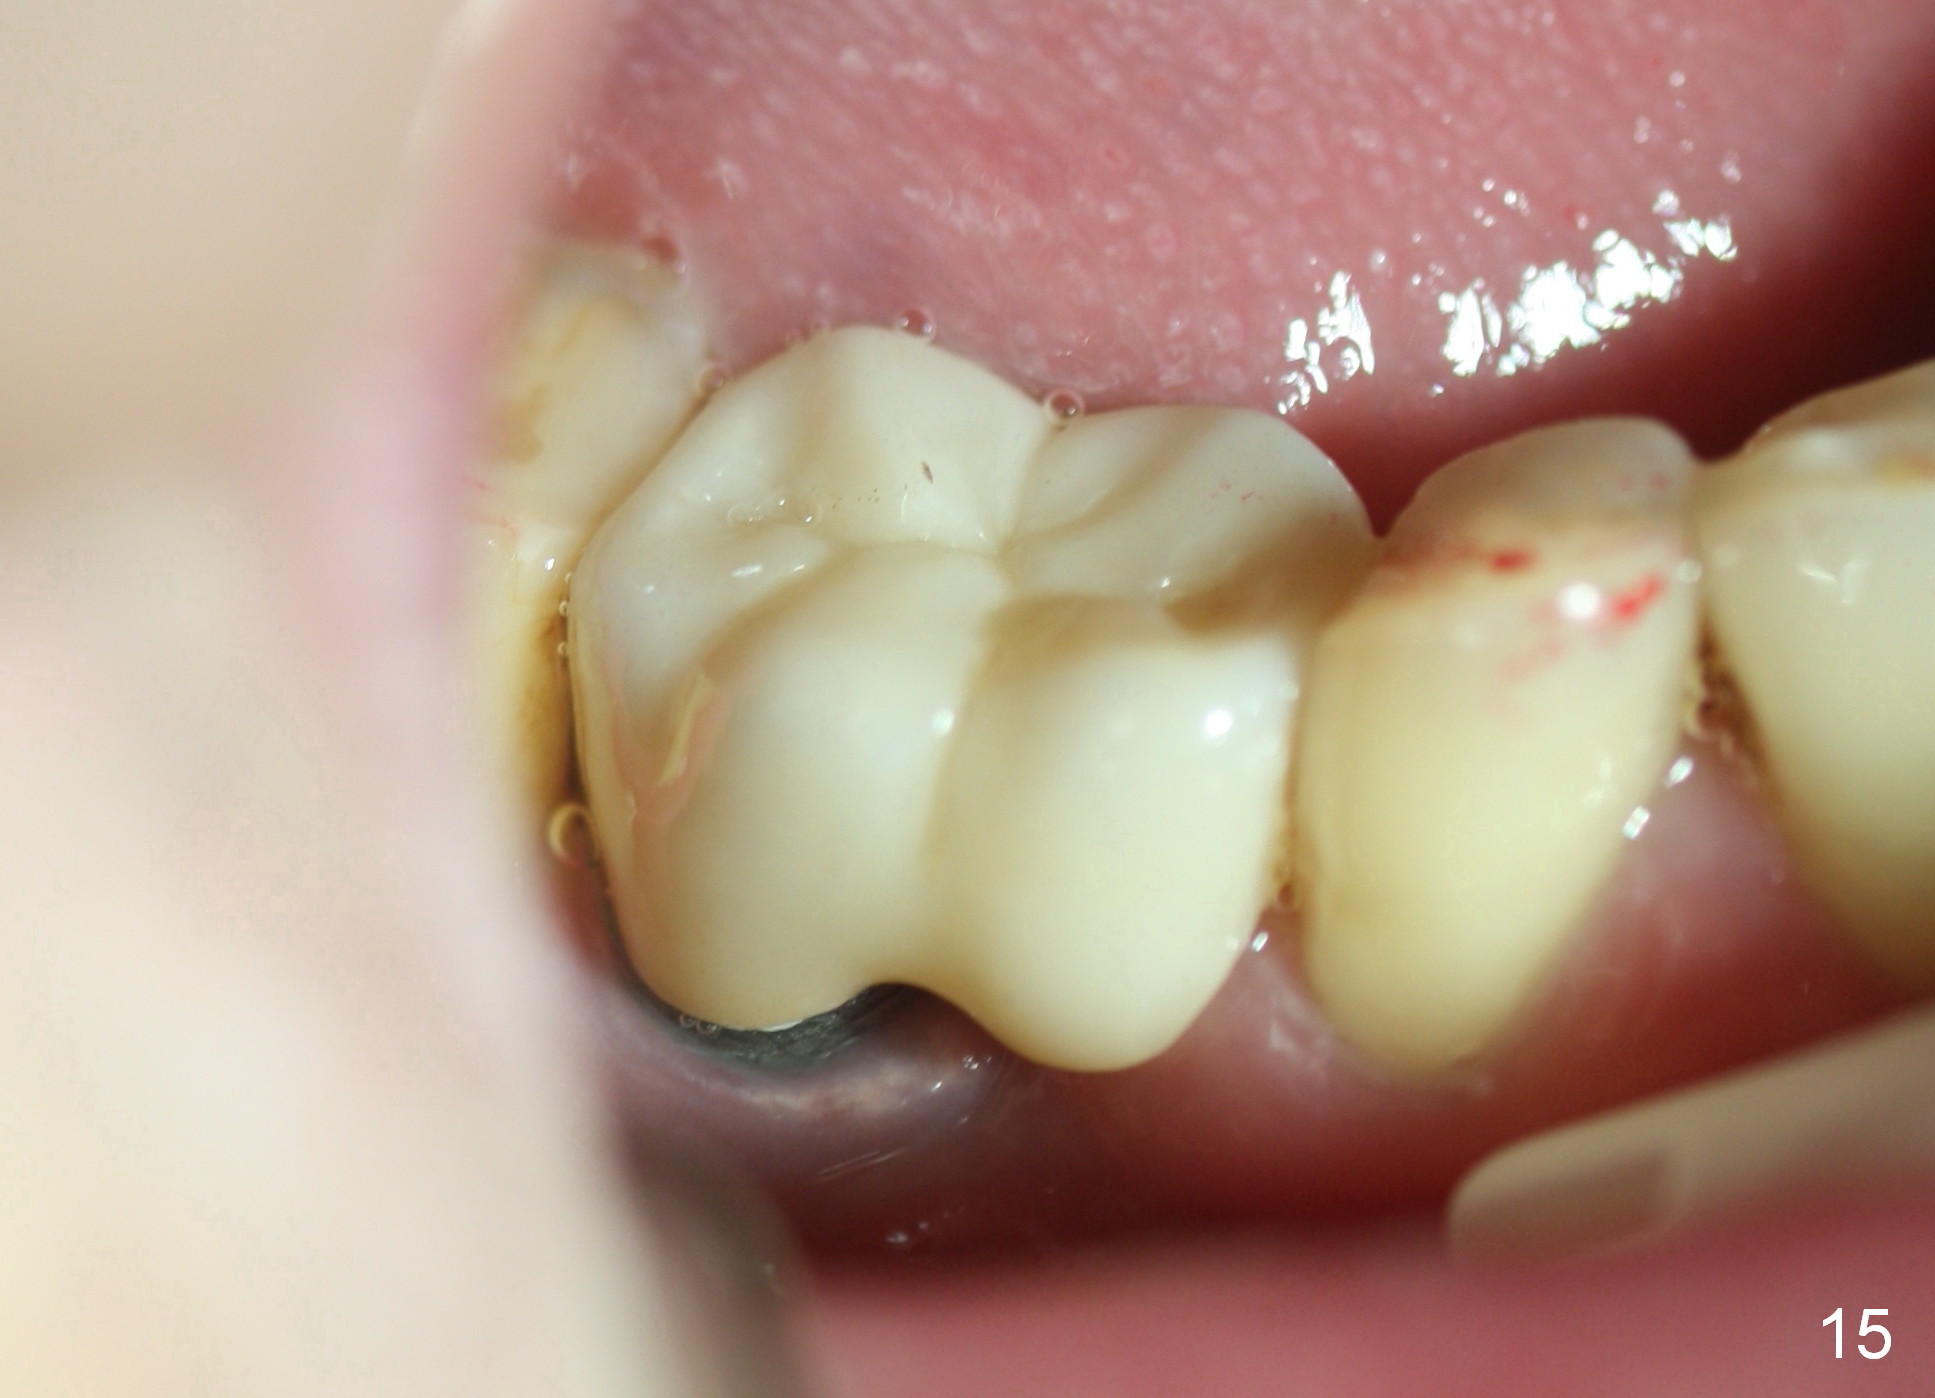

When the perio dressing is removed in office 24 days postop (Fig.9), the rough surface of the implant (R) is exposed buccally.  Normally the smooth surface should contact the gingiva (S).   Lingually implant/gingiva position is within normal limit (Fig.10).  The patient returns for restoration 4 months postop (Fig.11,12).  There is bone formation in the mesial socket and new bone appears to have grown toward the implant (Fig.11 <).  A straight abutment appears to be in the middle of the edentulous space (Fig.12 A).   But it is difficult to seat the crown.  Three months post cementation, the patient complains of food impaction mesially (Fig.10 ^), although bone density continues to increase in the mesial socket and there is no mesial coronal thread exposure (*).  Retrospectively the implant should be tried to be placed in the septum as much as possible to have a favorable restorative axis (Fig.14).  The crown is re-fabricated with larger mesial contact area.  It is temporarily cemented because of slightly loose distal contact (Fig.15).  A few days later, the patient requests permanent cementation, because although the distal contact is loose, it is easy to remove food.  Mesial food impaction is less likely, but it is more difficult to be removed.